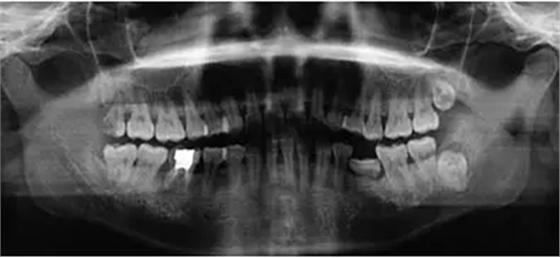

臨床檢查46面見大面積銀汞充填物,近中頰側(cè)部分牙體折裂至齦下約2mm,折裂部分已與牙體分離。46叩痛(-),松動度(-),牙齦(-),未探及牙周袋形成。曲面體層片示46髓腔內(nèi)及根管見高密度影像,未至根尖,根尖未見明顯陰影(圖1)。

圖1 拔牙術(shù)前曲面體層片 診斷46折裂牙(死髓牙)。